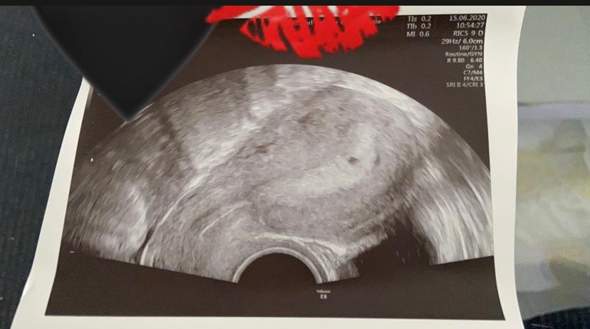

⭐️Willkommen im 3 Monat Deiner Schwangerschaft In der 9 SSW haben sich alle Organe des kleinen Fötus vollständig gebildet Er bewegt bereits seine Arme und Beine Unglaublich, oder?. 9 ssw zwillinge bauch Die hochwertigsten 9 ssw zwillinge bauch ausführlich analysiert!. 9 SSW Ultraschall Das ist zu sehen Das Baby ist in der 9 SSW ungefähr 16 bis 24 Millimeter lang Auf dem Ultraschall können Sie sogar schon sehen, wo beim Fötus später Finger und Zehen entstehen werden Wird jetzt die erste Ultraschalluntersuchung durchgeführt, lässt sich auch feststellen, ob vielleicht sogar Zwillinge unterwegs sind.

Huhu,heute berichte ich euch von der 9 und von der 10 SchwangerschaftswocheStriaSan in der Schwangerschaft* http//amznto/2hmzxx3StriaSan für nach der S. 9 SSW Ultraschall Das ist zu sehen Das Baby ist in der 9 SSW ungefähr 16 bis 24 Millimeter lang Auf dem Ultraschall können Sie sogar schon sehen, wo beim Fötus später Finger und Zehen entstehen werden Wird jetzt die erste Ultraschalluntersuchung durchgeführt, lässt sich auch feststellen, ob vielleicht sogar Zwillinge unterwegs sind. Erfahrungsberichte zu 9 ssw zwillinge bauch analysiert Um bestimmt behaupten zu können, dass die Wirkung von 9 ssw zwillinge bauch tatsächlich positiv ist, können Sie sich die Resultate und Fazite zufriedener Betroffener im Web anschauenEs gibt leider sehr wenige klinische Tests diesbezüglich, aufgrund.